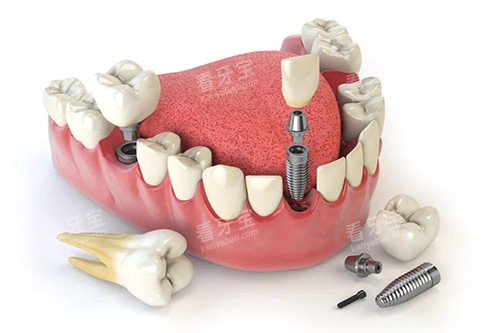

小创口种植牙技术也是苏和口腔的优势之一。

该技术通过微小的切口将种植体植入牙槽骨内,减少了手术创伤和术后疼痛,缩短了患者的修复时间。

同时,苏和口腔的医生们在种植牙手术方面有着丰富的经验,能够确保种植体的稳定性和可行性。